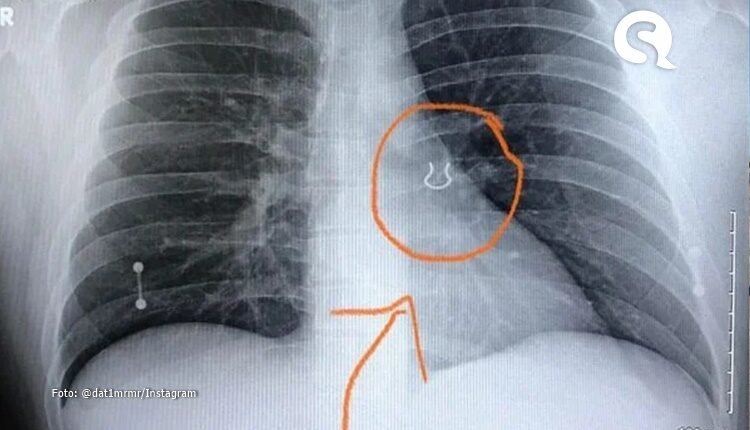

Em um relato feito nas redes sociais, o jardineiro Joey Lykins, 35 anos, conta uma situação inusitada que viveu no último mês. O americano foi socorrido após sofrer uma crise de tosse severa seguida de falta de ar, em um quadro semelhante ao de uma pneumonia. Ao chegar ao pronto socorro, descobriu que os sintomas eram provocados, na realidade, por um piercing alojado em seu pulmão há cinco anos.

Com as imagens do raio-x, os médicos suspeitaram que a joia se moveu ligeiramente para dentro do pulmão nos últimos anos, provocando só agora a sensação de bloqueio das vias aéreas e tosse aguda. O objeto foi retirado com uma broncoscopia, procedimento feito com um tubo que passa pela garganta normalmente usado para fazer o diagnóstico de infecções ou remover objetos dos pulmões.